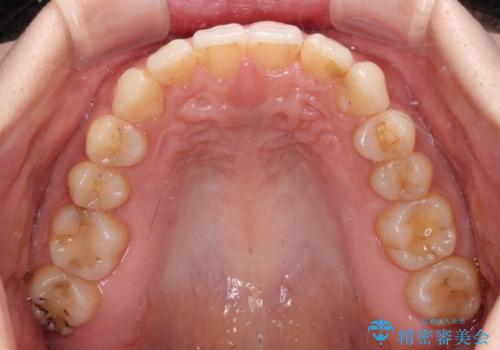

- 前歯のデコボコと深い咬み込みを気にして来院された患者様です。

インビザラインを用いて、前歯の叢生を解消するとともに、深い咬み合わせ(ディープバイト)を改善していくこととしました。

奥歯を後方に直立させることで深い咬み合わせを改善を図り、隠れていた下顎前歯が見えるほどになりました。